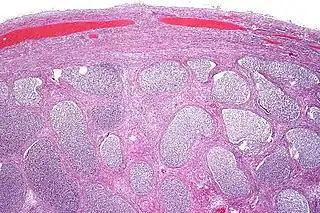

Epididimitis aguda con abundante exudado fibrinopurulento en los túbulos. | ||

El proceso inflamatorio involucrado y la subsecuente reparación del epitelio, los túbulos y el estroma del epidídimo, son una causa de infertilidad humana por factor masculino.